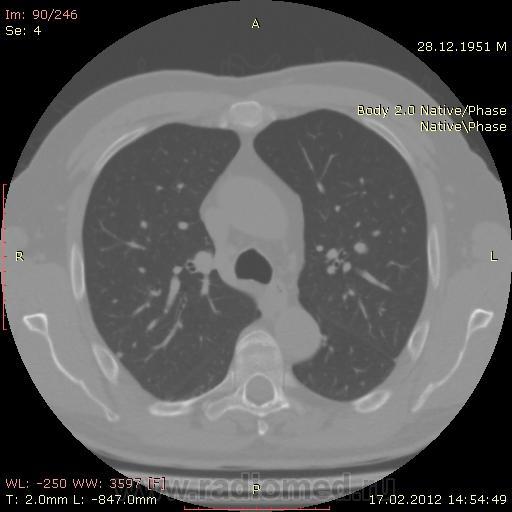

КТ.

В феврале 2012 года при очередном флюрографическом обследовании были обнаружены изменения в лёгких. По собственной инициативе было сделано КТ лёгких.

На первый взгляд - метастазы. А так, если родственник, искать выходы на МСКТ.

Согласен с Андреем Юрьевичем - наиболее вероятно - это метастазы...исключите первичное новообразование почки.

Согласен с коллегами, внешне вылитые метастазы. Но почему нет контраста? Не соли мочевой кислоты точно. Учитывая анамнез можно думать о неопроцессе почек.

Повторяюсь (мнение озвучил еще до КТ и до Ваших коментов) но это отдаленные по времени метастазы рака почки....увы....и даже если будет найден еще один первичный очаг, то все равно это - метастазы...опять - увы....